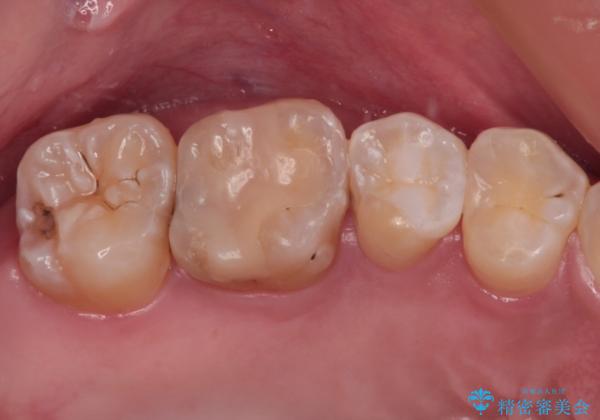

治療後は物が挟まることもなく、フロスが引っかかったり出血したりすることが減りました。